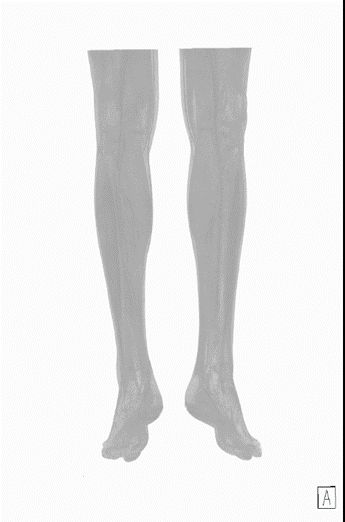

8. 類DSA成像:

傳統(tǒng)DSA成像有創(chuàng)而且操作復(fù)雜、掃描范圍受限。

SOMATOM Force 突破技術(shù)界限,將血流評估覆蓋范圍擴大至80cm,特別適合大范圍下肢血管疾病診斷,一次掃描一次注射即可無創(chuàng)精確判斷病變,更加精確地制定臨床決策,選擇合理的治療方法。

△80厘米無創(chuàng)CT DSA,影像決策診療